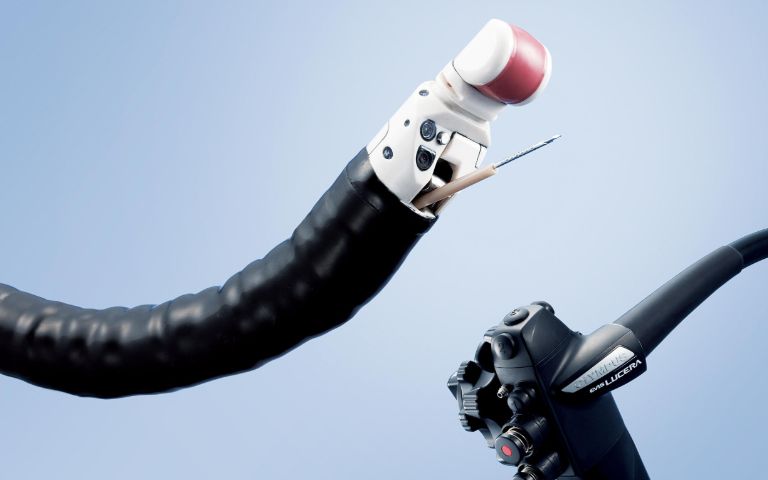

▲図1:コンベックス型超音波内視鏡

内視鏡の先端に超音波観測装置がついた特殊な内視鏡です(図1)。口から挿入して、胃や十二指腸から膵臓や胆管、胆のうを超音波装置にて観察する検査です(図2)。